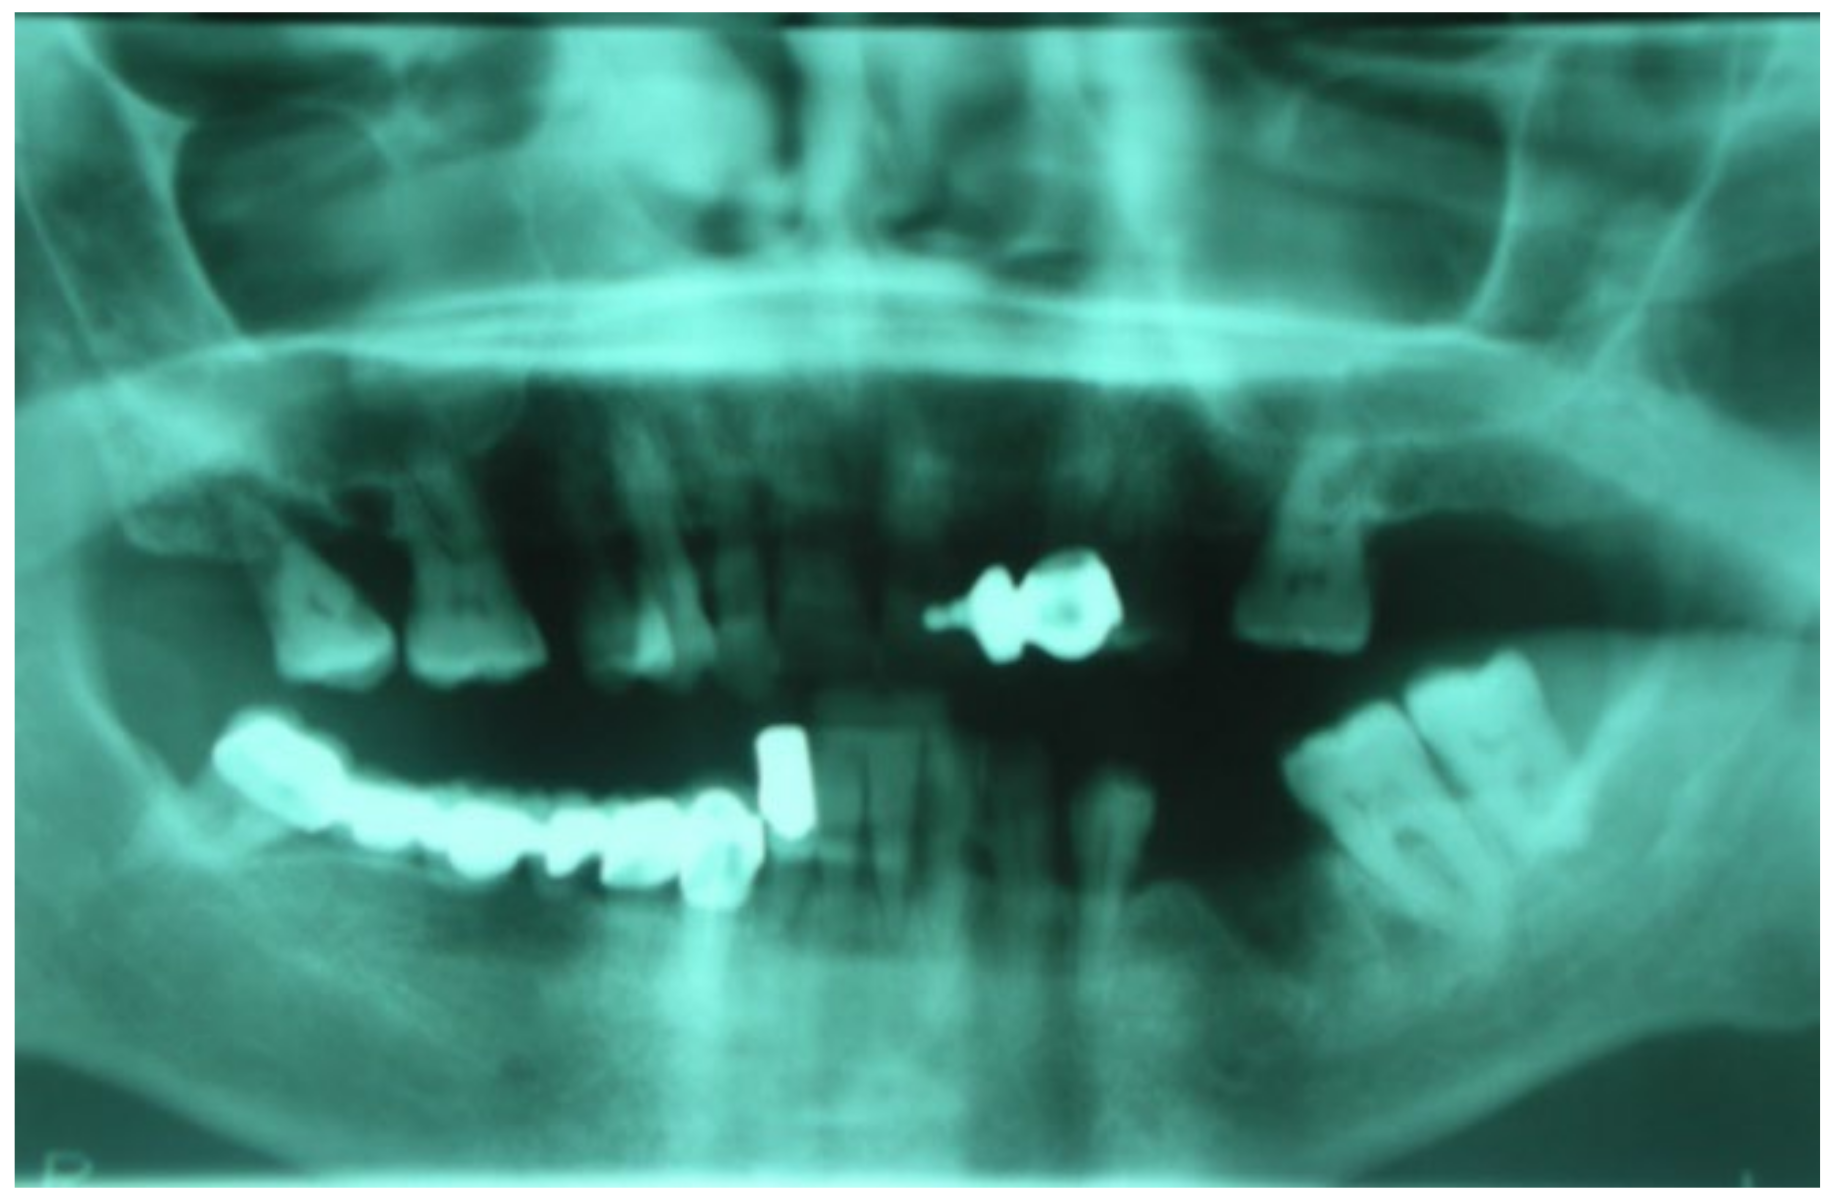

3.1. Clinical Case 1

3.2. Clinical Case 2

3.3. Clinical Case 3

3.4. Clinical Case 4

3.5. Clinical Case 5

3.6. Clinical Case 6